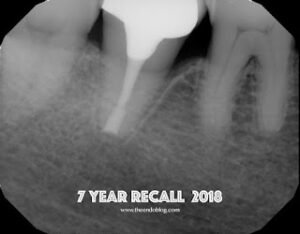

A seven year recall finds tooth #31 asymptomatic and fully functional. While the mesial bone looks irregular, there is no periodontal pocket. If you look at the initial photo of the extracted tooth, you can see the periodontal ligament, but there appears to be an area where the ligament had been lost. There was not visible fracture on that area of the root at that time. My assumption is that the pdl may not have ever reformed in that area – causing the current radiographic appearance.